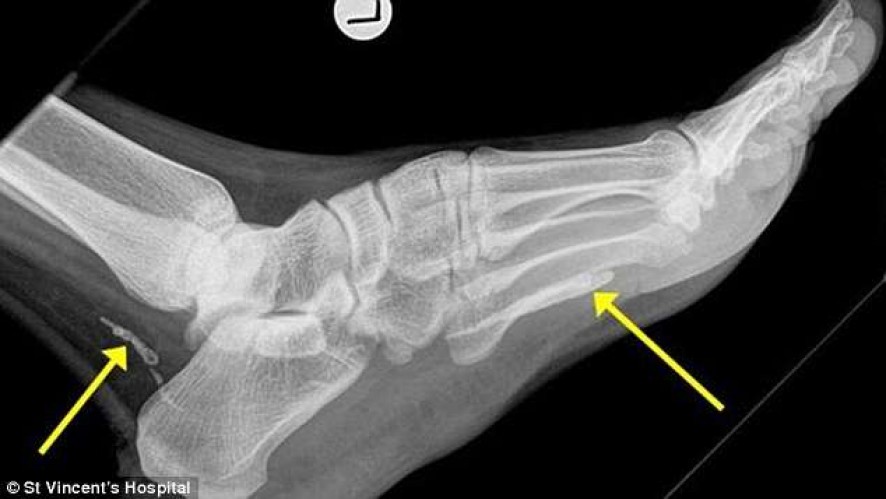

Midianews Apos Um Exame De Raio X Homem Descobre Verme Africano Em Seu Pe

Midianews Apos Um Exame De Raio X Homem Descobre Verme Africano Em Seu Pe from www.midianews.com.br